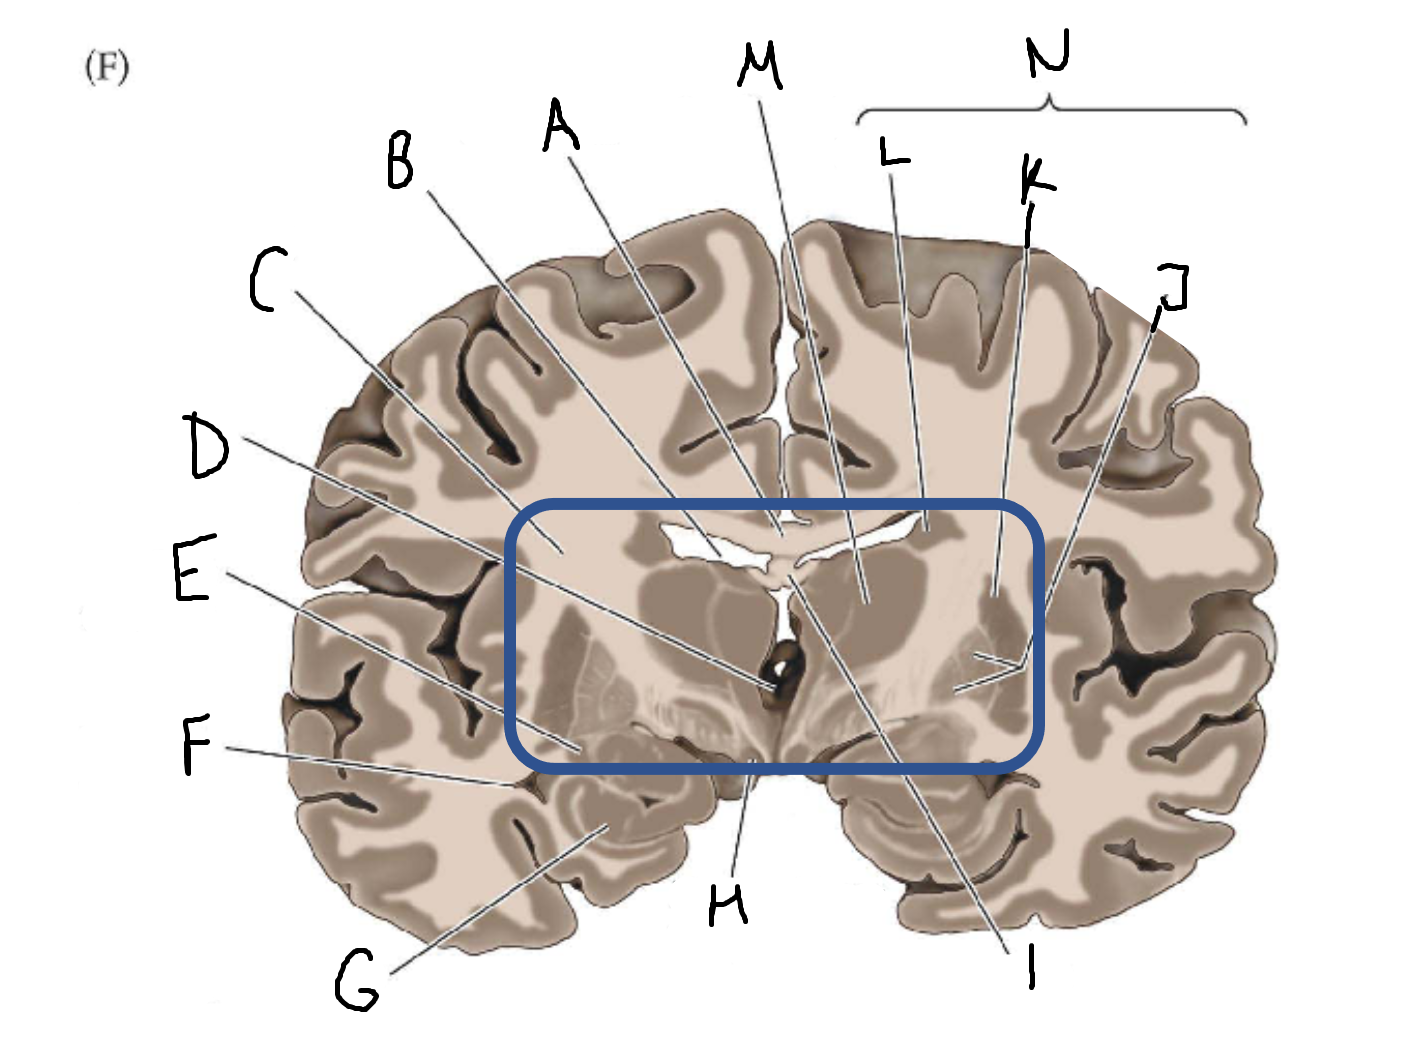

A

corpus callosum

B

lateral ventricle

C

internal capsule

D

third ventricle

E

tail of caudate nucleus

F

lateral ventricle

G

hippocampus

H

mammillary body

I

fornix

J

globus pallidus

K

putamen

L

caudate

M

thalamus

N

basal ganglia